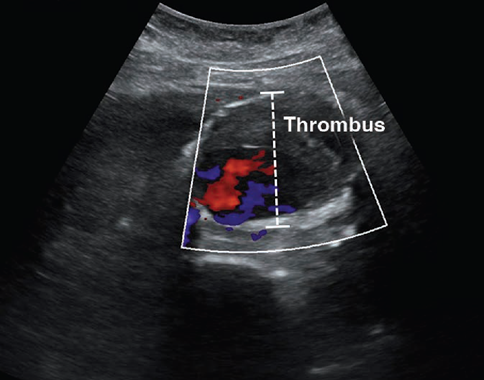

POCUS has excellent ability to detect AAA, which is defined by a diameter exceeding 3 cm when measured from outer wall to outer wall (Fig. 3).

A systematic review and meta-analysis found POCUS to have a sensitivity of 99% and specificity of 98%, when performed by emergency medicine physicians [23]. Although POCUS can accurately determine the presence or absence of AAA, the ability to detect signs of rupture is poor, which is largely due to the limited ability to visualize the retroperitoneum. Findings that indicate rupture include deformation of aneurysmal shape, heterogeneity or focal discontinuity of the intraluminal thrombus, focal disruption of the outer wall, hypoechoic areas in the paraaortic region, and hemoperitoneum [24].